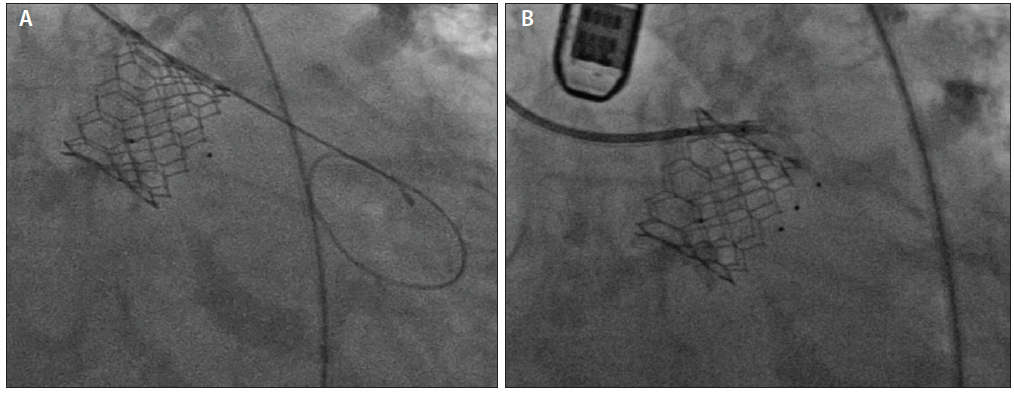

Figure 6. Three-dimensional TEE guiding a mitral PVL procedure for an anterolateral defect at the 10 o’clock position along the mitral annulus (A). The catheter and wire are shown crossing in the interatrial septum and approaching the defect. Panel B shows the formation of a transcatheter wire rail. A steerable guide catheter was used to guide a hydrophilic guidewire across the PVL into the left ventricle, which was then directed through the aortic valve and snared in the ascending aorta. A transcatheter wire rail is seen after the hydrophilic wire was snared in the ascending aorta and externalized via femoral artery access (C). Over the wire, a catheter was advanced across the PVL into the left ventricle, and the first AVP II was deployed across the defect. The wire was maintained in place after the device was deployed to allow access to the PVL for further devices. Panel D shows the final image of the mitral PVL case with three AVP IIs deployed.

Once the defect is crossed with a guide or sheath, the plug is placed and released in a fashion similar to aortic defects, with TEE and fluoroscopic imaging used to rule out interaction with prosthetic valve leaflets. TEE is used to assess the degree of PVL reduction. If the defect is large and a single vascular plug does not provide adequate closure, placement of multiple plugs within the same defect may be necessary using an “anchor wire” technique. In this technique, the previously described single-catheter technique is adjusted by advancing a shuttle sheath across the defect and maintaining a stiff wire across the defect while the plug is deployed. The stiff wire is then maintained in place after the release of the plug, and then the shuttle sheath may be advanced alongside the plug over the stiff wire (Figure 6D). It is important to note that a larger access sheath size may be necessary to accommodate the passage of multiple devices and wires, and compatibility may be an issue.